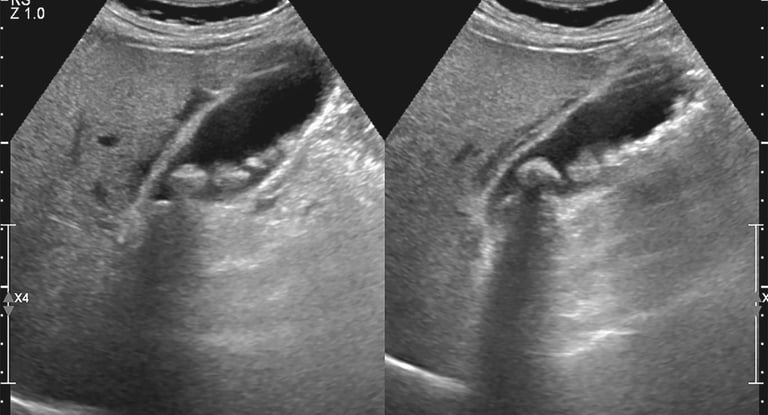

A lot of people go through life without realizing that tiny stones may already be forming inside their gallbladder. These are called gallstones. Most people never experience any symptoms and may only be diagnosed incidentally with routine whole abdominal ultrasound. However, some of my patients do experience severe abdominal pain that sends them to my clinic, or worse, to the emergency department. Understand gallstone is the main topic for today to help patients recognize early symptoms and seek proper medical care before complications occur.

Doc Damian, what are gallstone, why are they bothersome to some people? Gallstones are hardened deposits of digestive fluid that form in the gallbladder, a small organ just below the liver. The main function of the gallbladder is to store bile, which helps digest fats. When the substances in bile become imbalanced, they can crystallize and form stones. I’m sure, you did not know that there are 2 types of gallstones: cholesterol stones and pigment stones. Cholesterol stones are the most common type, about 80% of cases – they form when bile contains too much cholesterol. The latter, pigment stones, are smaller and darker colored which is made up of bilirubin – and are often associated with liver disease or blood disorders.

As I had mentioned earlier, gallstones may be silent for a long period of time until pain is experienced by the patient. So, what type and characteristic of pain do we need to watch out for? The pain is in the right upper quadrant of the abdomen, that occurs after eating fatty meals and can radiate to the right shoulder or scapular area that may be associated with nausea/vomiting or bloated. Pain will only occur when a stone is already blocking the duct. If left untreated, gallstones can lead to serious complications such as acute cholecystitis (infection of the gallbladder), pancreatitis, obstruction and jaundice – when this are observed, urgent medical attention is warranted.